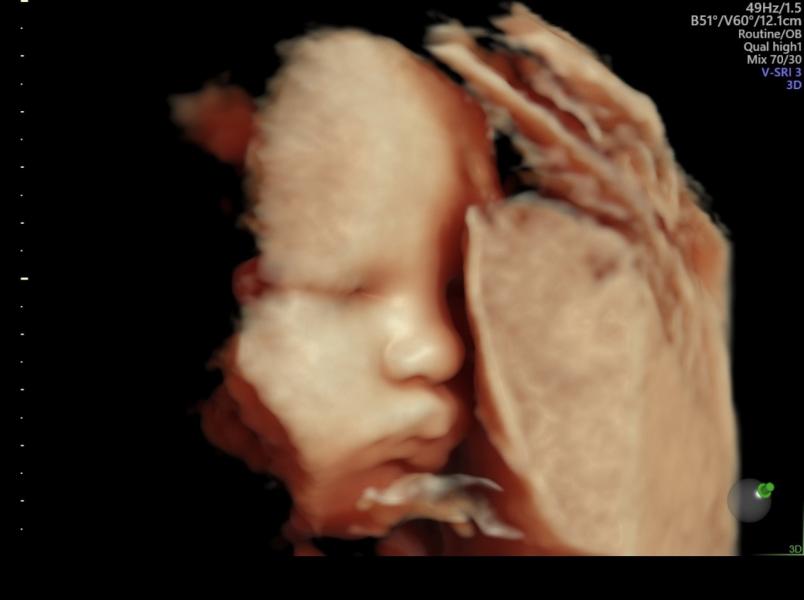

Вот и 38 недель.

Сходили на узи, малышок во всей красе показал свое лицо, а это значит что он еще очень высоко. И узист говорит что места у него еще там предостаточно👌😁